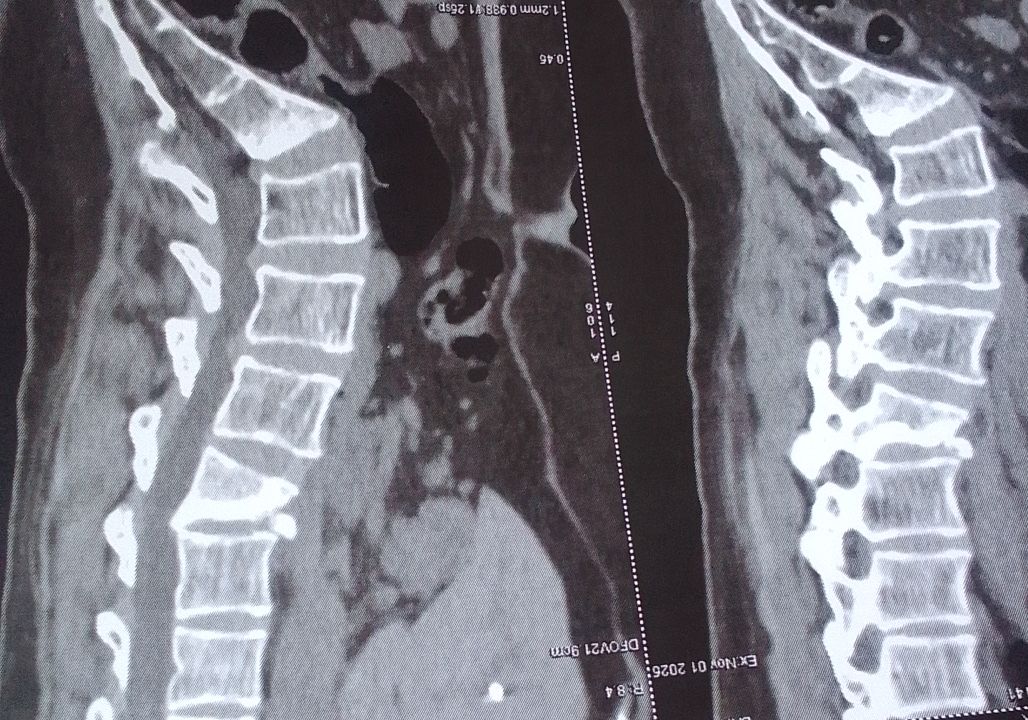

كسر في فقرات الظهر ولا يوجد تنمل في الارجل ولا شلل

كسر في فقرات الظهر ولا يوجد تنمل في الارجل ولا شلل هل تحتاج الى جراحة وما نوع الجراحة ادا امكن

كسر انضغاطي من الدرجة الثالثة ، وهو كسر غير ثابت، يحتاج الى جراحة لرد الكسر وتثبيت الفقرات. والف سلامة ولابد من عمل رنين مغناطيسي قبل اجراء الجراحة 0 2025-11-12T12:07:58+00:00 2025-11-12T12:07:58+00:00

كسر انضغاطي من الدرجة الثالثة ، وهو كسر غير ثابت، يحتاج الى جراحة لرد الكسر وتثبيت الفقرات. والف سلامة ولابد من عمل رنين مغناطيسي قبل اجراء الجراحة

بالنسبة لكسور الفقرات هذا يعتمد على نوع الكسر ودرجة الثبات إذا كان مافيش خلل عصبي فيمكن الاعتماد على العلاج الغير جراحي لكن يجب فحص صور السكانير للتأكد من نوع الكسر 0 2025-11-05T03:46:52+00:00 2025-11-05T03:46:52+00:00

بالنسبة لكسور الفقرات هذا يعتمد على نوع الكسر ودرجة الثبات إذا كان مافيش خلل عصبي فيمكن الاعتماد على العلاج الغير جراحي لكن يجب فحص صور السكانير للتأكد من نوع الكسر